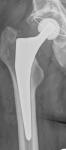

War nur ein Spaß, aber ihr lasst euch nicht täuschen! :daumenhoch:

Und hier nun komplett:

...deine stramme Hüfte :D ...schwing das Bein Uwe!

Schön, dass du wieder unter uns weilst! :)

.....tanzen werde ich wohl nie so richtig lernen, trotz neuer Hüfte! :wacko:

.....ich freue mich auch auch dass ich wieder bei Euch bin! :cool: